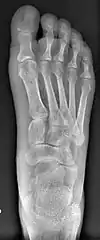

- For recurrence correction after osteotomy procedure (Fig. 8)

Late deformity recurrence can happen after osteotomy (bone-breaking) procedures because osteotomy surgeries do not specifically stabilize first metatarsal bone.